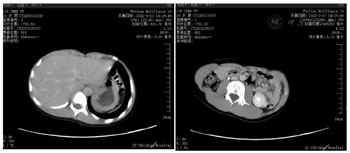

上腹部增强CT(本院):1.右侧腹膜后胰头后方不均质肿块影,内合并出血,考虑嗜铬细胞瘤?2.左侧肾上腺内支略粗;3.双肾盂略饱满,双肾均为双支肾动脉供血,见图1。

术前头颅MRA报告:1.右侧额颞顶岛叶、右侧基底节区片状异常信号,考虑缺血梗死灶;2.右侧大脑中动脉纤细,分支减少,SWI右侧大脑中动脉M1段呈条状低信号,考虑右侧大。脑中脉栓塞?见图2。